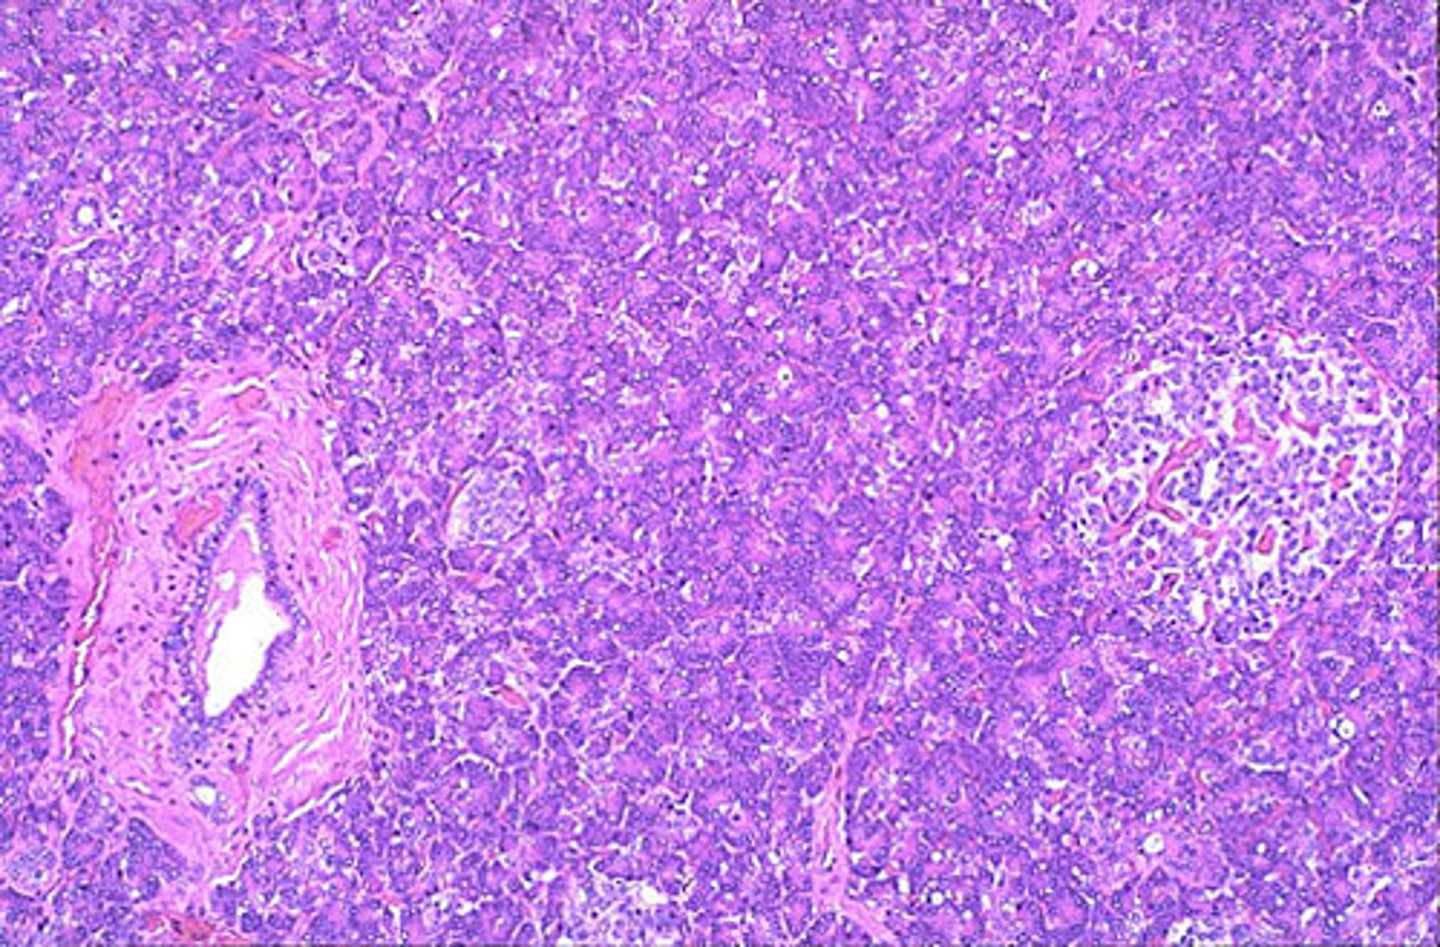

pancreas

label each part